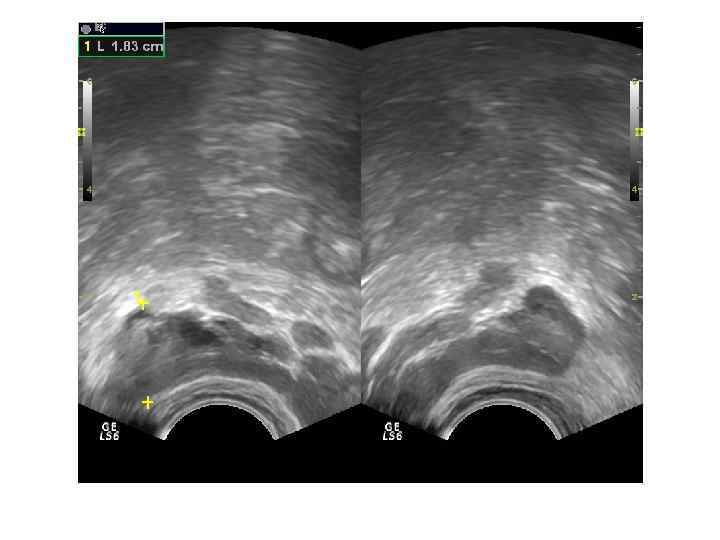

Прямые признаки опухоли: Наличие узла опухоли в железе (гипоэхогенные участки с неровными и нечеткими контурами неправильной формы в периферических зонах – 25%). Косвенные признаки: Асимметрия органа. Нарушение целостности капсулы. Деформация контура. Асимметрия семенных пузырьков.

Прямой признак наличия опухоли удается выявить только в 25 -30% случаев. В 65% эхогенность опухолевых узлов неотличима от прилежащей диффузно-измененной ткани. Только стадии Т 3 и Т 4 позволяют в 100% случаев уверенно определить наличие опухоли. При стадиях ниже Т 3 основываться только на ультразвуковую картину нельзя!

Распространенность опухолевого процесса После визуализации узлов опухоли необходимо определить их количество, локализацию, эхогенность, размеры, контур, симметрию органа, наличие инвазии капсулы, прорастание в окружающие ткани и органы. Выявление метастатического поражения лимфатических узлов: осмотр лимфоузлов забрюшинного пространства возле подвздошных сосудов, по ходу аорты и нижней полой вены. Метастазы отдаленных органов: типичны метастазы в кости, лимфоузлы надключичных областей.

ЦДК и ЭДК опухолевого поражения простаты Большинство авторов отмечает усиление и асимметрию сосудистого рисунка в зоне опухолевого роста.